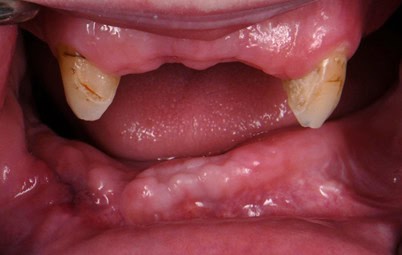

Two months later, the full prosthodontic evaluation revealed severely limited opening with an inter arch maximum distance of around 18mm (from alveolar ridge to ridge) (Fig. 2A and 2B). The maxillary tuberosities were 2mm superior to the retromolar pads bilaterally. The goal of maintaining the cuspids served as a reference during the mandibular repositioning and subsequent use as a potential abutment for future overdenture treatment.

Figure 2B: Intraoral photo at the patients maximum mouth opening